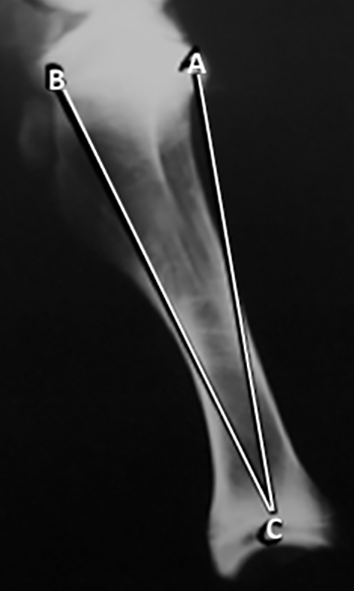

En las radiografías antero-posterior de la tibia se trazaron y midieron 2 líneas (Figura 5): 1.       A-C: desde la región lateral del platillo tibial al centro de la tibia distal. 2. B-C: desde la región medial del platillo tibial al centro de la tibia distal. En las radiografías laterales de la tibia se trazaron y fueron medidas 2 líneas (Figura 6): 1. B-C: desde la región anterior del platillo tibial al centro de la tibia distal. 2. A-C: desde la región posterior del platillo tibial al centro de la tibia distal.

Figura 6: : Radiografía de perfil de tibia. Líneas desde el platillo tibial al centro de la tibia distal. B-C: al centro de la tibia distal. A-C: al centro de la tibia distal.

Figura 5: : Radiografía anteroposterior de tibia. Líneas desde el platillo tibial al centro de la tibia distal. A-C: al al centro de la tibia distal. B-C: al centro de la tibia distal.